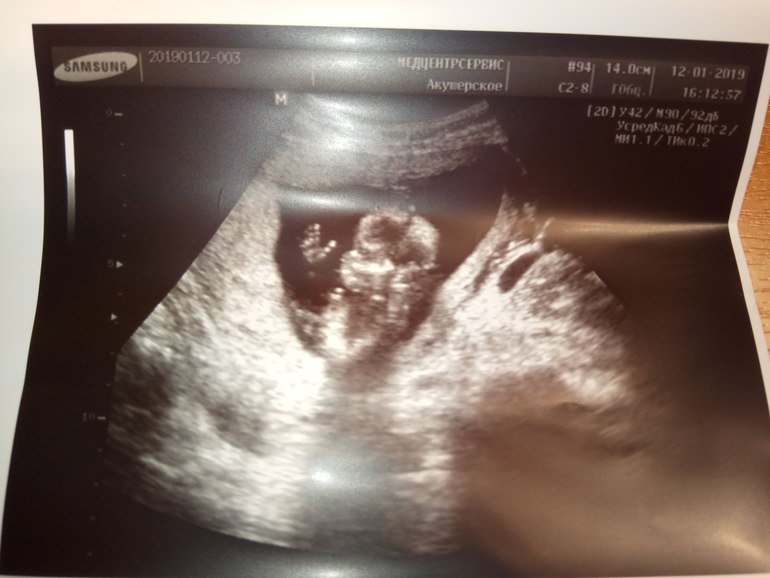

14 недель

СамочувствиеВсем, привет! У нас заканчивается 14 неделя и начинается 15😀. Сегодня ходили все вместе на УЗИ (муж и сын,как группа поддержки). Врач сначала все измерила у малыша, всё посмотрели))) малыш не стал стесняться и сразу сел по турецки и показал свой причиндал))) у нас будет мальчик!!! Как я и хотела))) Постоянно сны снились, что у меня рождается сын. И вот все подтвердилось))) После всех измерений, доктор пригласила мужа и сына со словами : пойдёмте смотреть Николаевича))) муж сразу понял, что мальчик и стоял как мешком пришибленный. Малыш, как только услышал голоса папы и сына помахал нам!!! Так сказать, привет, земляне)))

по "техническим данным" : срок беременности 13,6. Ктр 92, носовая кость 4,8, что соответствует 14-15 неделям беременности. Сб 154, плацента по передней стенке, но не очень высоко пока. Врач сказал не волноваться, все поднимется ещё. Вес малышонка 100гр. Пдр по месячным 15/07/19. Пдр по УЗИ 07/07/19. Тонус не большой есть, продолжаем пить магний.